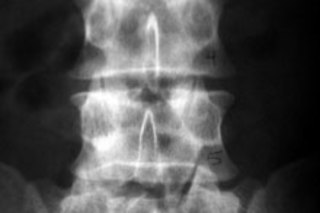

Geron's treatment is intended to help patients with mid-back spinal cord injuries who are paralyzed below the site of the damage. The cells will be injected within the first two weeks after the injury.

Geron ... turns embryonic stem cells into precursors of neural support cells called oligodendrocytes. The precursor cells would be injected into the spinal cord at the site of the injury. The hope is that the cells will repair the insulation, known as myelin, around nerve cells, restoring the ability of some nerves to carry signals. While this is not expected to allow people to rise from their wheelchairs, it may conceivably restore some movement or sensation. [The New York Times]